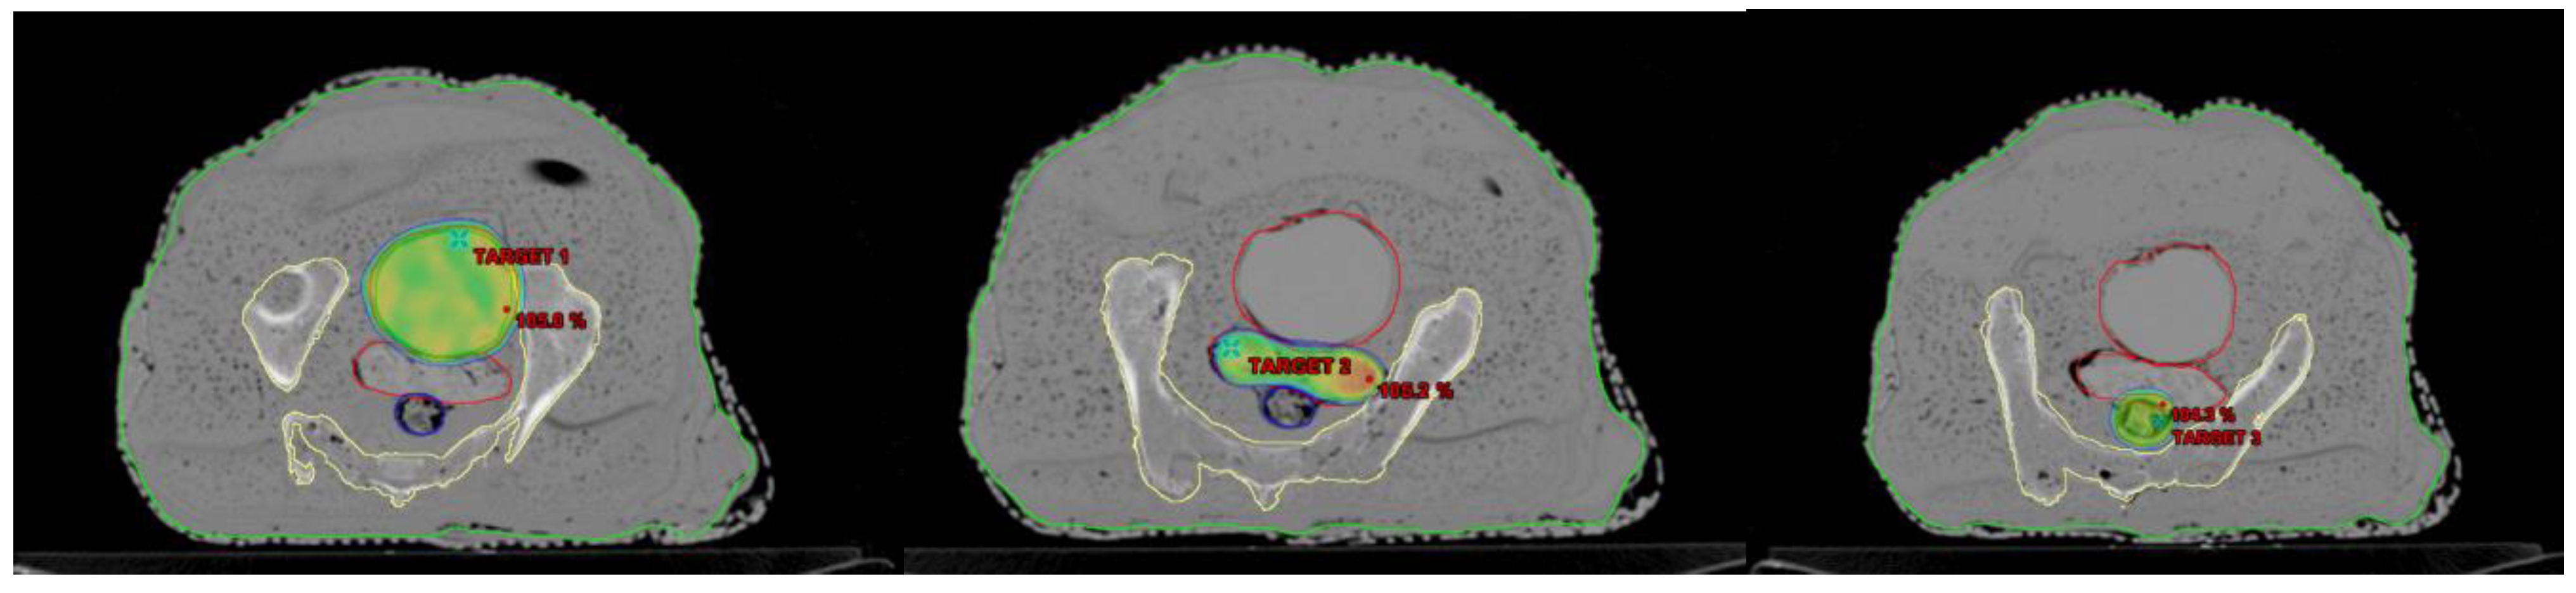

To determine how accurately the finished phantom product represents a real patient, the AHFP phantom was scanned with a CT scanner (Toshiba Alexion 16 multi-slice CT scanner) at 120 kVp and 250 mAs with a slice thickness of 2 mm. The CT images were transferred to the Eclipse treatment planning system (version 11.0.31) (Varian Medical Systems, Palo Alto, CA, USA). The CT images of the phantom were compared to CT images of randomly selected cervical cancer patients with similar scanning parameters (120 kVp, 250 mAs, and 2 mm slice thickness), which are shown in Figure 2A,B.

Figure 2.

HU value representation on CT images of (A) a real female patient and (B) the AHFP phantom.

Overall, there is good agreement between the measured CT number (HU) and relative electron density (RED) of the AHFP phantom and the patient groups. Table 2 displays the findings of the comparison between measured CT numbers from a sample of patients from our institution who were selected at random and the CT numbers of the phantom. Hence, it was observed that the AHFP fabricated for this study matched both the qualitative and quantitative aspects of the CT evaluation.